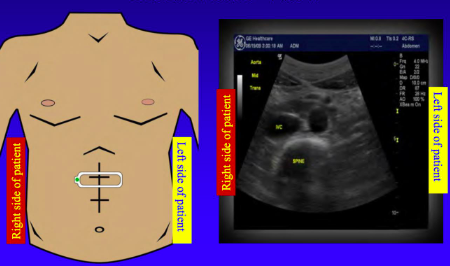

In \________ view markers points to the patient right side

transverse

The probe marker is towards the patient's \__________ when the probe orientation is transverse

right

When the ultrasound probe is transverse (cross-sectional) the left of the picture is ______

lateral (right)